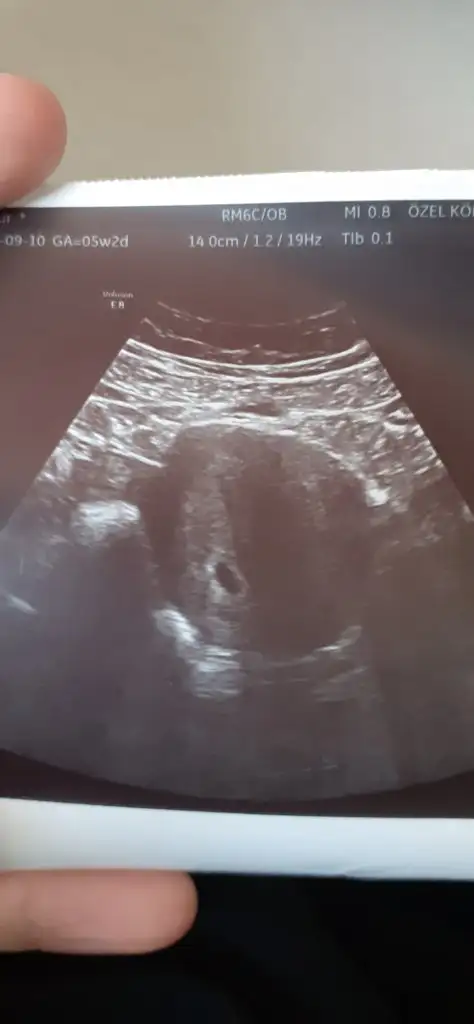

Hayırlı olsun darısı başımıza inşKızlar bugün kesemizi gördük çok şükür. Sat 26 hazirandı. 3 temmuz olarak değiştirdi. 5 haftalık dedi. 2 hafta sonra gel kalp atışını duyarız dedi